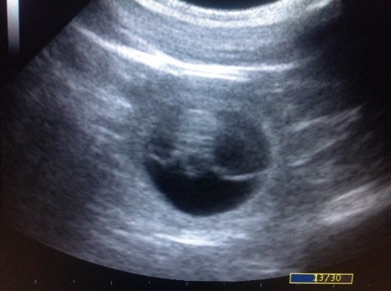

4.9.2017 32.deň

26.9.2017 54.deň